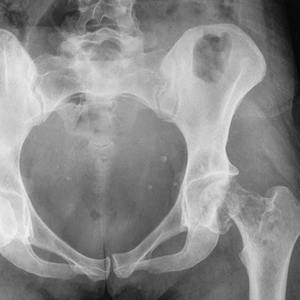

Постановка точного диагноза основывается на проведении прицельной рентгенограммы тазобедренного сочленения. При рентгенографии, лечащий врач оценивает целостность костных структур и легко выявляет наличие переломов. В сложных диагностических случаях используют компьютерную томографию, позволяющую получить объемное и высокодетализированное изображение суставного сочленения.